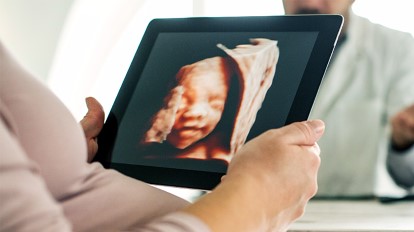

4、可以留下永久的纪念

如果你是一个特别喜欢收集孩子珍贵时刻的人,建议去做四维,可以拍一张胎儿的照片,等宝宝出生后做一个对比,将是非常有纪念意义的。

四维彩超的基础还是二维,是一种超声波对腹部扫描,形成的图像用软件处理,就成了我们看到的立体图像,对胎儿是没有伤害的。